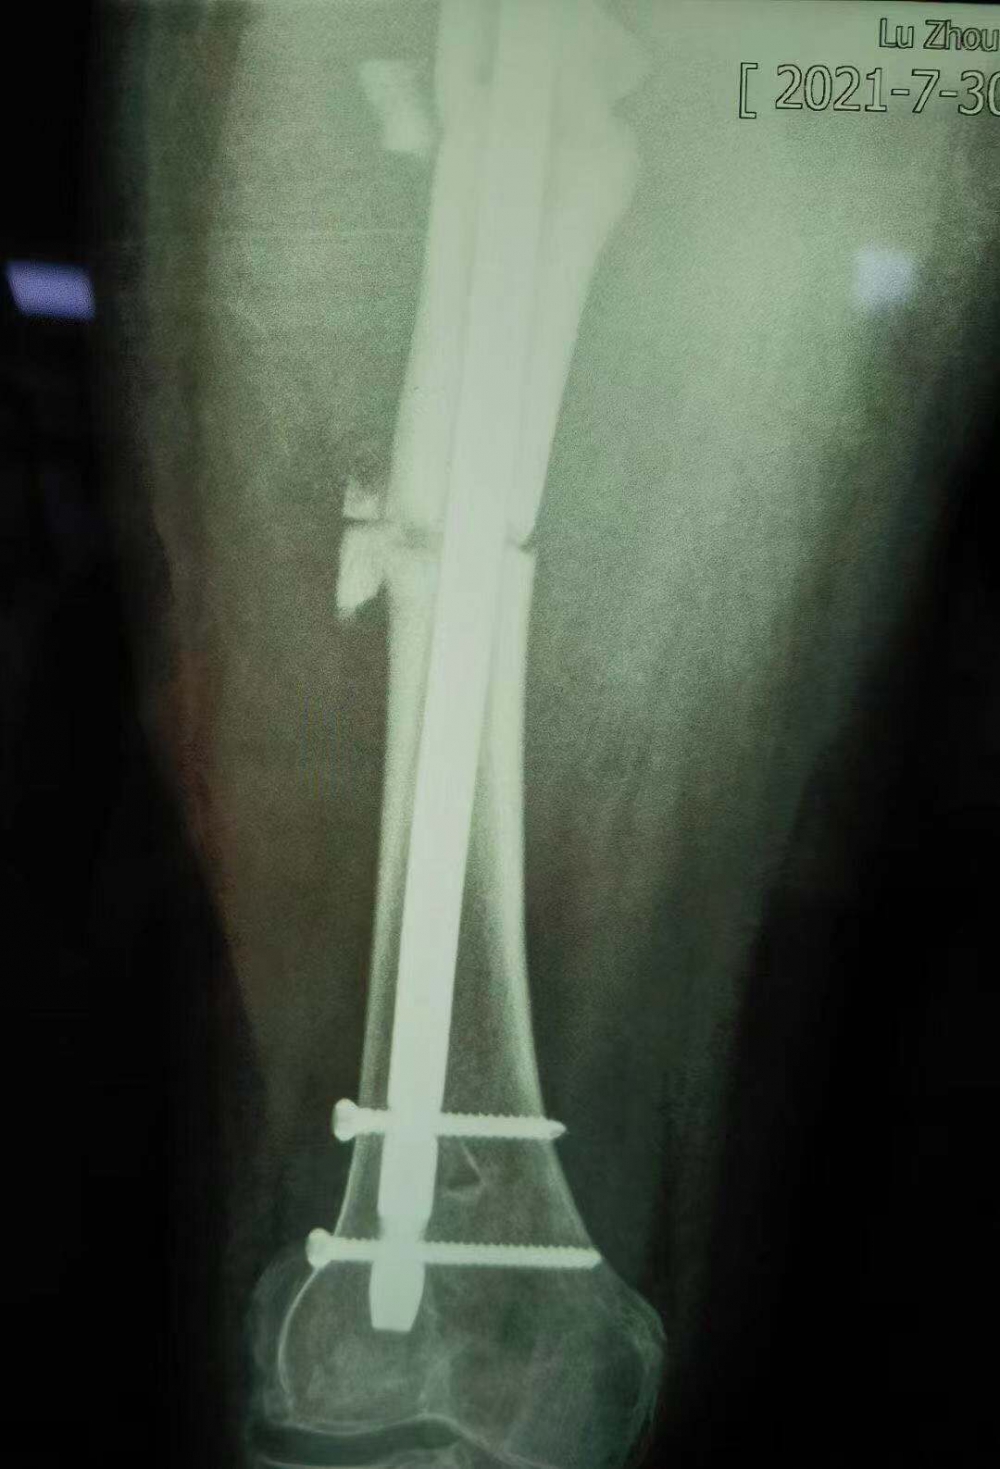

術(shù)后拍攝的X光片

但因張女士屬于股骨上段骨折畸形以后手術(shù)歸正,整個(gè)股骨頭的負(fù)重區(qū)已經(jīng)發(fā)生了一些改變,髖關(guān)節(jié)關(guān)節(jié)炎也可能存在,因此張女士還需進(jìn)行后續(xù)的康復(fù)性治療和護(hù)理。